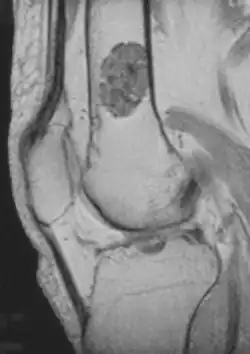

Diagnosis is by X-ray, CT scan and sometimes MRI.[4] Most occur as a less than three centimetre size single tumor. When several occur in one long bone or several bones, the syndrome is called enchondromatosis.[4]

- magnetic resonance imaging (MRI)[7] – a diagnostic procedure that uses a combination of large magnets, radiofrequencies, and a computer to produce detailed images of organs and structures within the body. This test is done to rule out any associated abnormalities of the spinal cord and nerves.